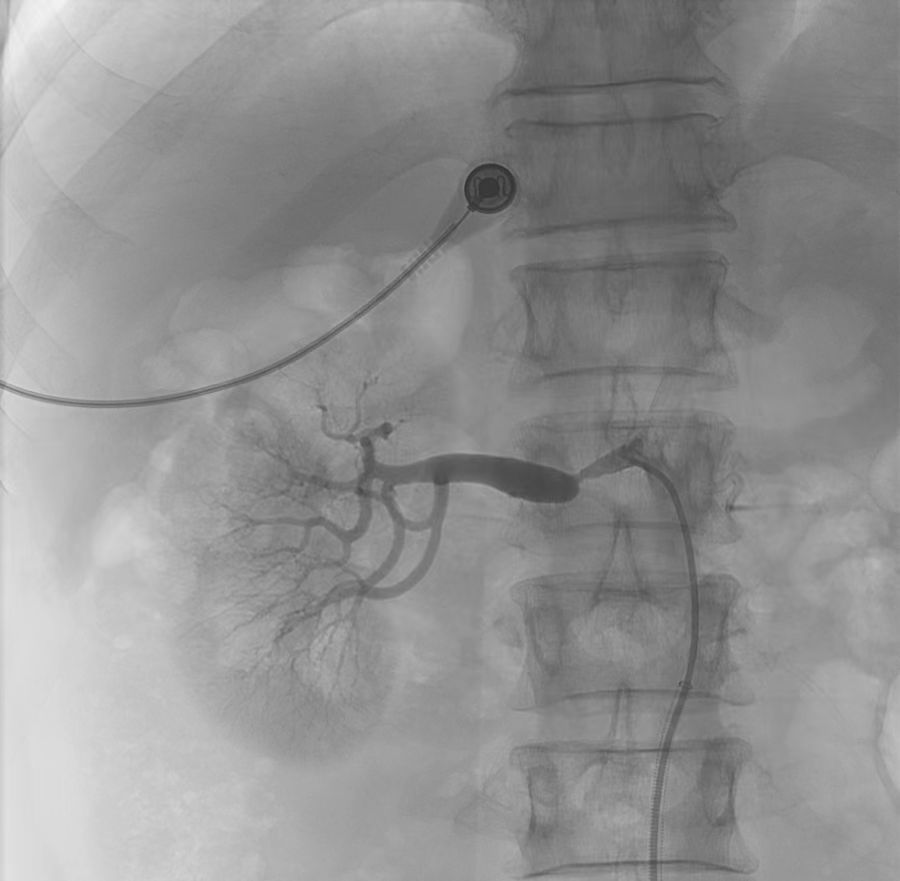

微信图片_20240411093454.jpg

血管CTA图像(红色标记为右肾动脉狭窄部位)